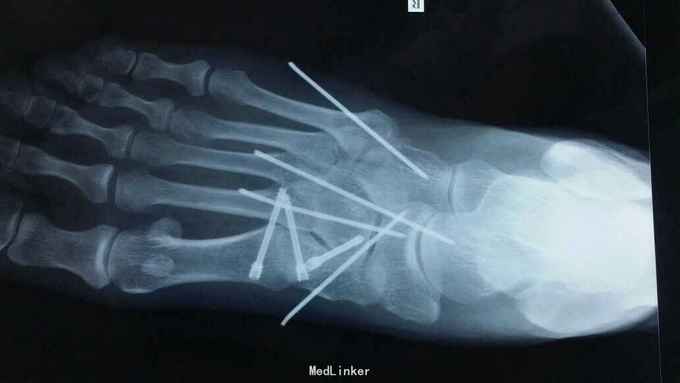

主诉:右足外伤后肿痛,活动受限11天。 现病史:患者于2015年11月10日摔伤右足,当即肿痛,活动受限,急去当地医院拍片及入院行石膏固定保守治疗,效果不佳,为求进一步治疗来诊我院,经门诊阅片及查体后以“右足多发骨折,脱位,韧带损伤”为诊断收入院。

查体:右足略肿胀,畸形明显,足背压痛广泛阳性,可触及骨擦音及骨察感,活动受限,末梢各趾活动自如,足背动脉清。 辅助检查:大致正常。

诊断:右足多发骨折伴跖跗关节脱位,韧带损伤 治疗:患者入院后,完善检查,于2015年11月25日行手术治疗,现切口愈合良好。